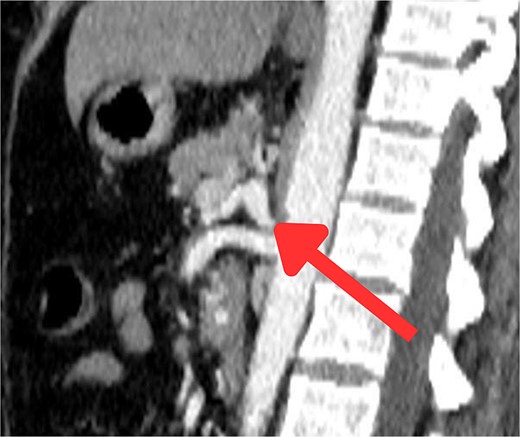

The CT scan confirmed a Dieulafoy’s lesion from the left phrenic artery (Fig. 2a and b) and showed collateral vascular channels around the pancreas with near-complete celiac trunk compression by the median arcuate ligament (Fig. 3). She underwent left phrenic artery embolization without complications, while asymptomatic celiac artery compression was treated conservatively. A follow-up endoscopy showed no bleeding or ulcers (Fig. 1d). Later, she developed severe left flank pain, and a contrast-CT revealed splenic vein thrombosis with infarction (Fig. 4), which was treated conservatively. Additionally, an incidental finding of left pleural effusion was drained. Rising inflammatory markers were managed with analgesics and IV antibiotics. She was discharged with outpatient follow-up, and at her 10-day visit, she reported improvement, stable hemoglobin, and normal inflammatory markers. She was satisfied, and a follow-up endoscopy was planned in 2 weeks.

Sagittal abdominal CT angio shows complete obliteration of the celiac trunk due to compression from the medical arcuate ligament.

Endoscopic treatments for Dieulafoy lesions include thermal (heat probe, argon plasma), injection (epinephrine, norepinephrine), and mechanical methods (banding, hemoclips), often combined for better outcomes [2]. If these methods fail, selective arterial embolization can be used as an alternative, involving angiography to identify the bleeding artery, which is then embolized with glue or coils [5]. Surgical intervention remains a final option with a high success rate for refractory cases [4]. The CT scan, in this case, confirmed a Dieulafoy’s lesion from the left phrenic artery, treated with embolization, and showed near-complete celiac trunk compression by the median arcuate ligament, treated conservatively. Median arcuate ligament syndrome (MALS) is a rare condition affecting 2 in 100 000, caused by celiac artery compression. It may have genetic and environmental causes and presents with bloating, weight loss, nausea, vomiting, and abdominal pain [6]. MRA and Doppler ultrasound are useful, but CTA is preferred for its detailed images, despite radiation and contrast risks [6]. MALS leads to significant hemodynamic changes, potentially causing pancreaticoduodenal aneurysms, splenic infarction, and splenic vein thrombosis due to reduced celiac artery flow. Severe compression can result in mesenteric ischemia and visceral infarction, with the spleen being especially vulnerable [7]. Treatment of MALS involves surgically decompressing the celiac artery. Minimally invasive methods generally result in faster recovery and less pain but have their risks. If stenosis persists, additional procedures like stenting may be necessary [6, 8].